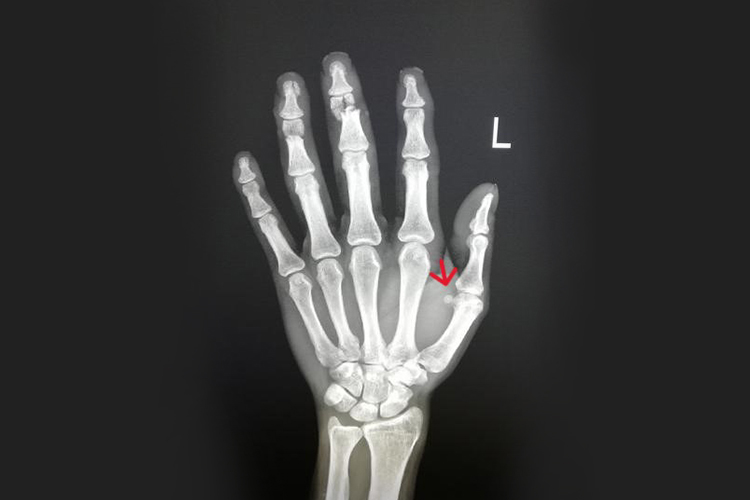

拇指内侧的籽骨位于拇指掌骨小头上,关节面向手一侧的锯齿处。籽骨肌腱合并入关节囊内,籽骨结节和邻近骨构成关节的延伸部分,裸出面常有软骨层覆盖。籽骨是一种位于肌腱或韧带内的卵圆形结节状小骨块,直径大多只有几毫米。

籽骨有减少摩擦力、替代并组成关节囊、增加力臂等功能。根据个体的不同,部分人群在第五掌指关节、第二掌指关节等部位也可出现籽骨。此外,籽骨由于结构特点,易出现移位、脱位,以及特发性炎症等异常改变。